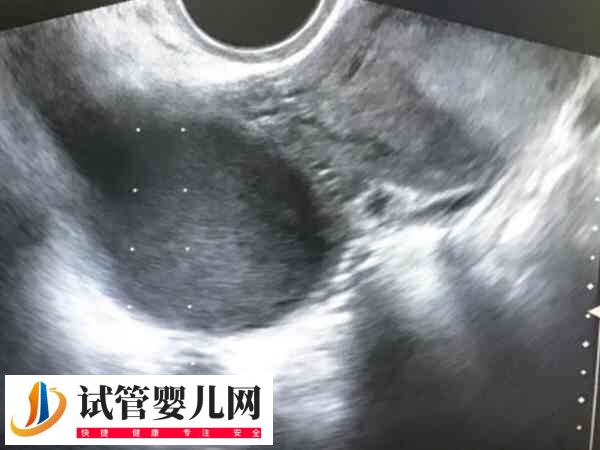

在试管治疗中,如果患者存在子宫腺肌症,即使通过试管婴儿技术移植两个鲜胚,也并不能保证一定会怀上双胎。这是因为子宫腺肌症患者的子宫内膜的厚度和健康状况较差,可能不足以维持2个鲜胚的着床和妊娠,不过因个体差异较大,所以具体情况还要看个人的身体状态。

子宫腺肌症体做试管移植两个新鲜胚胎不一定会成功怀上双胞胎。这是因为一般试管移植前,医生会对患者的身体状况进行评估,从而决定是否同时移植两个胚胎。反之,可能一个胚胎成功植入,也可能两个胚胎移植后都植入失败。所以子宫腺肌症患者移植两个新鲜胚胎后能否怀上双胞胎,是因人而异的。

毕竟子宫腺肌症是一种特殊的子宫内膜异位症,容易导致女性月经紊乱,月经量增加,经期延长等不良情况,受孕后流产和早产的风险也相对较高。所以建议子宫腺肌症患者,做试管婴儿移植2个鲜胚时,一定要遵医嘱进行相关治疗,以此才能提高怀孕的几率。